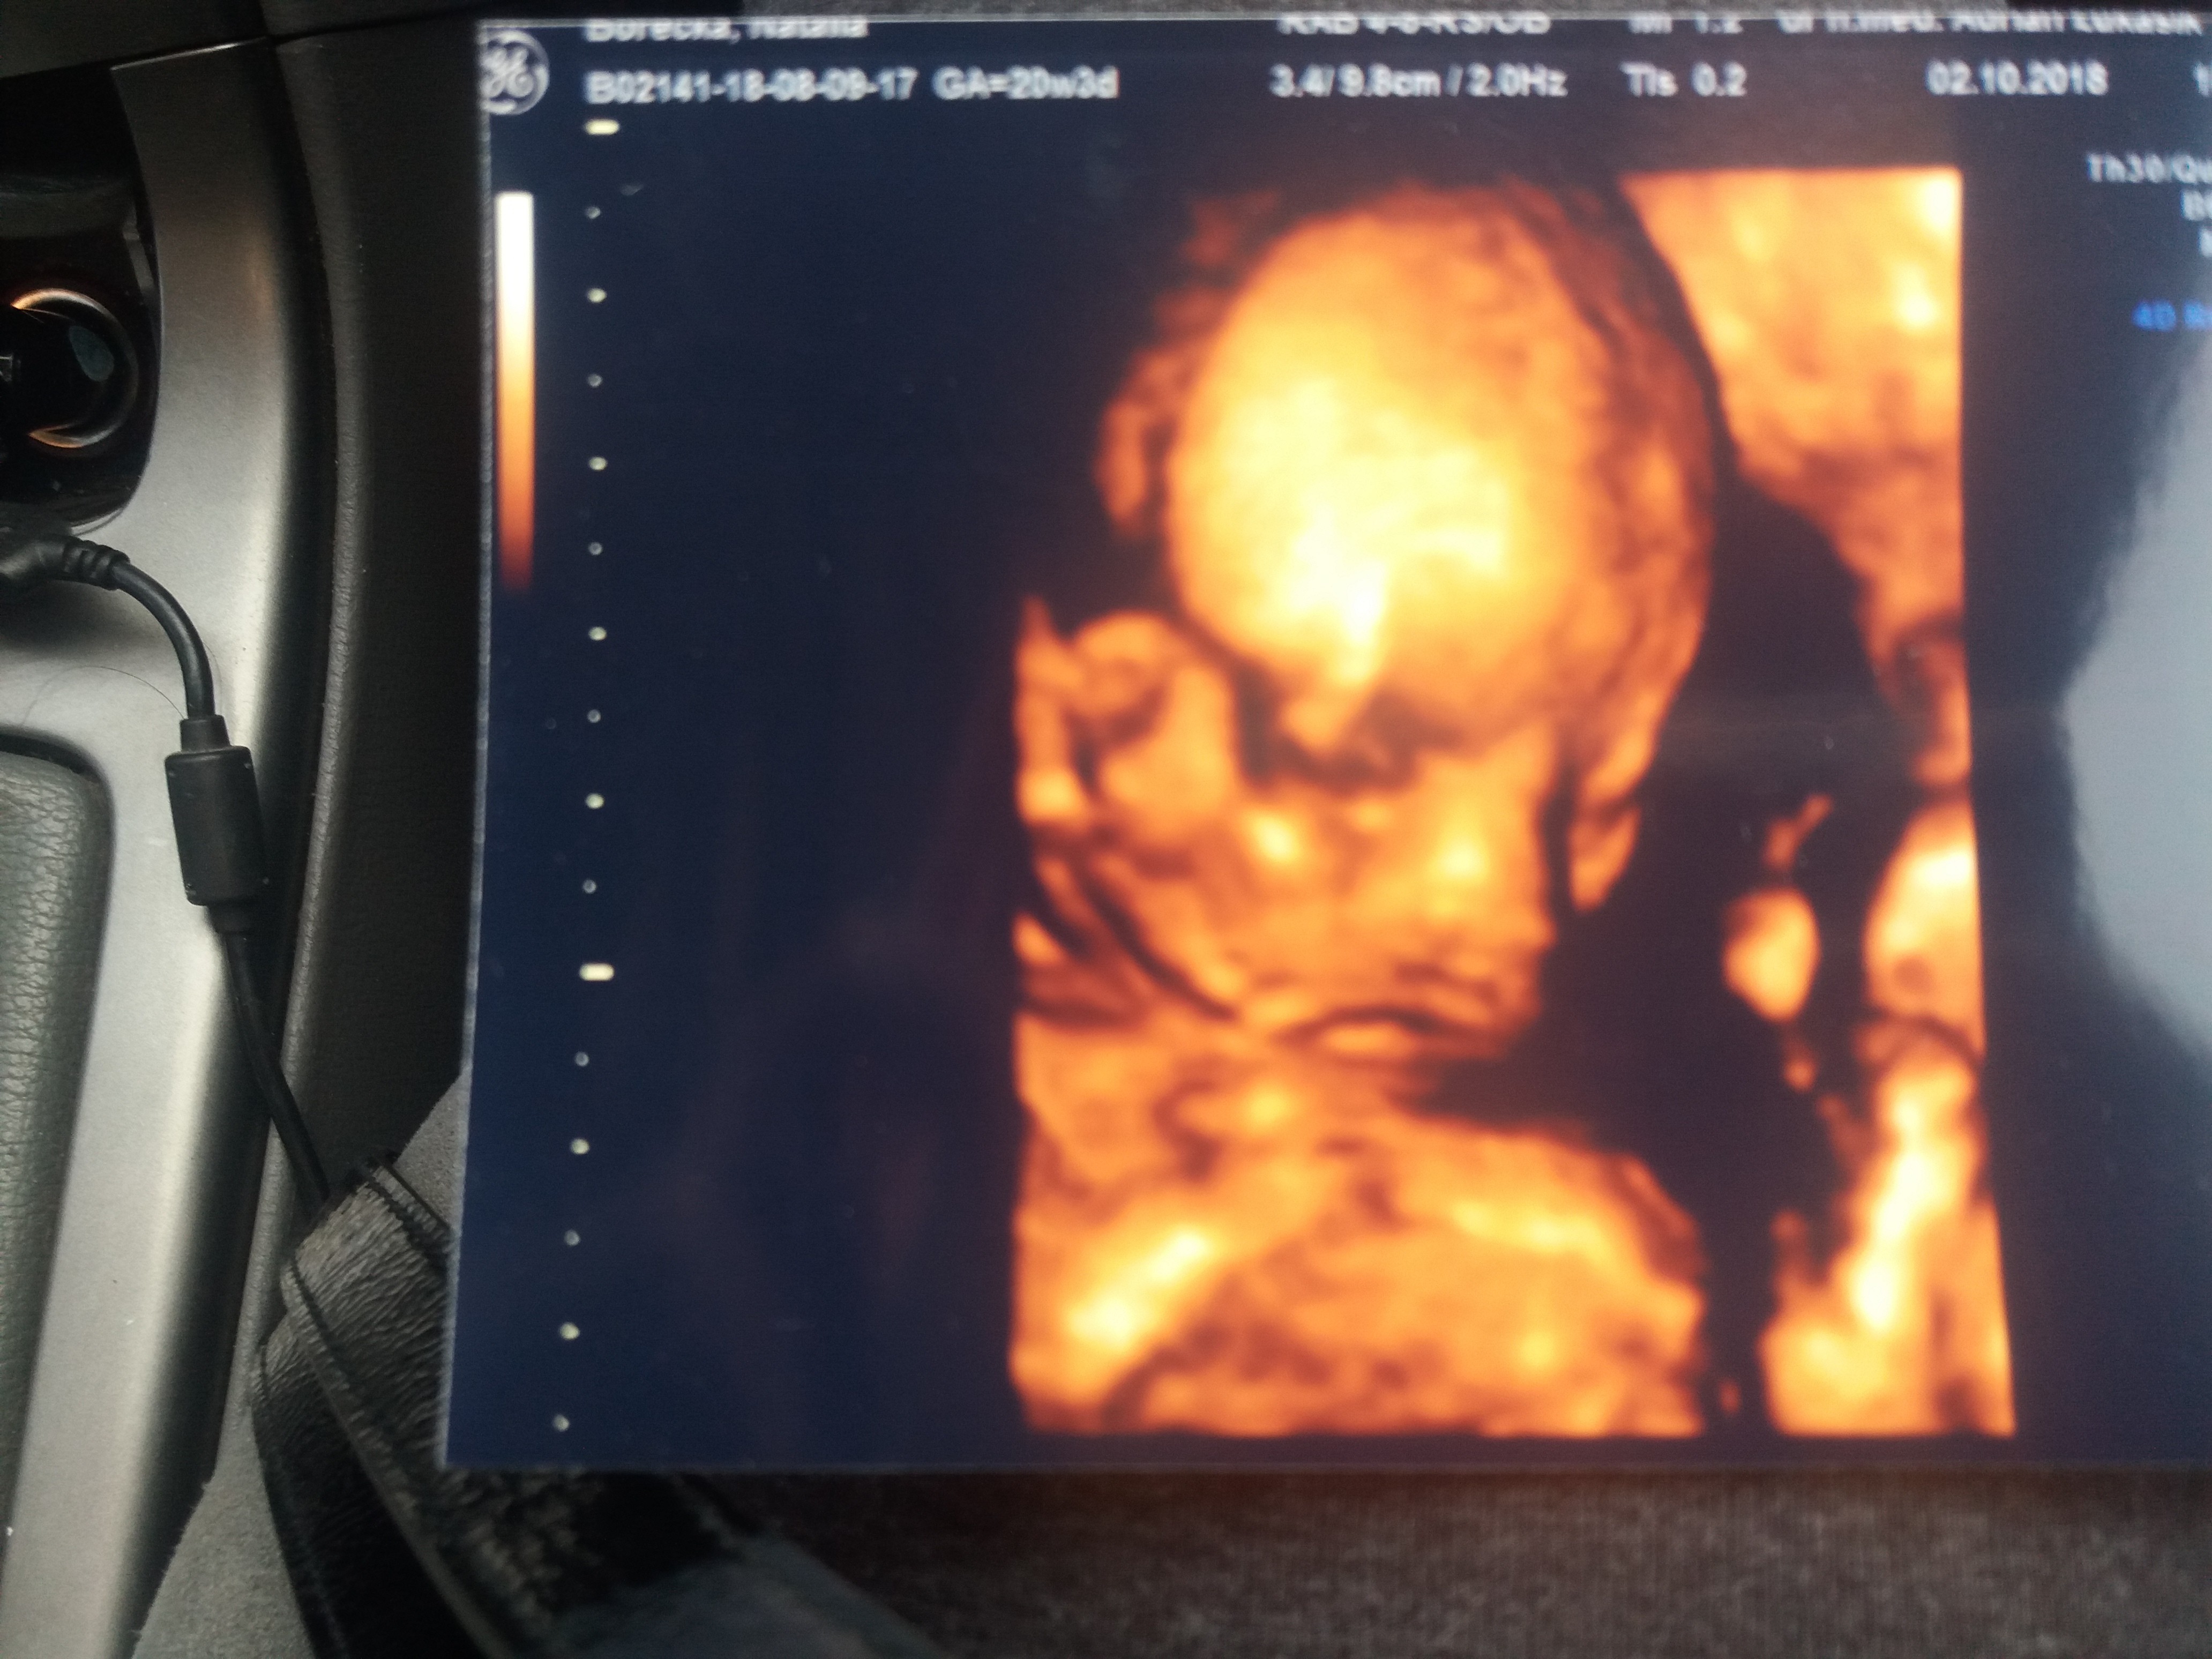

Więc u nas wszystko w porządku, wszystkie pomiary w normie i dziewczynka na 100% według lekarzaKochana daj koniecznie znac![]()

Ale super [emoji7][emoji7][emoji7]Więc u nas wszystko w porządku, wszystkie pomiary w normie i dziewczynka na 100% według lekarza![]()